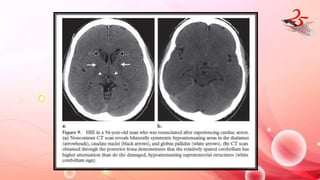

HYPOXIC ISCHEMIC ENCEPHALOPATHY

• CAUSE : Result of cardiac arrest /drowning/asphyxiation

IMAGING FINDINGS:

• Mild HIE : water shed zones

• Severe HIE : grey matter structures like cerebral cortex , BG and

hippocampi.

• Brainstem and WM are typically spared.

• CT : Diffuse edema , decreased attenuation of the cortical gray matter

with loss of normal gray matter–white matter differentiation, BG and

Thalamus

• WHITE CEREBELLUM SIGN : diffuse cerebral damage results in lower attn.

of cerebral parenchyma , compared to cerebellum and BG which are

spared – POOR PX

• Earliest finding(after 2 hrs) : Increased SI of the affected areas on

DW

• T2W : hyperintensity and swelling of affected areas ( after 24 hrs)

• Delayed : T2 hyperintensity in subcortical WM

HYPOXIC ISCHEMIC ENCEPHALOPATHY •CAUSE : Result of cardiac arrest /drowning/asphyxiation IMAGING FINDINGS: • Mild HIE : water shed zones • Severe HIE : grey matter structures like cerebral cortex , BG and hippocampi. • Brainstem and WM are typically spared. • CT : Diffuse edema , decreased attenuation of the cortical gray matter with loss of normal gray matter–white matter differentiation, BG and Thalamus • WHITE CEREBELLUM SIGN : diffuse cerebral damage results in lower attn. of cerebral parenchyma , compared to cerebellum and BG which are spared – POOR PX

• 20.

HYPOXIC ISCHEMIC ENCEPHALOPATHY •Earliest finding(after 2 hrs) : Increased SI of the affected areas on DW • T2W : hyperintensity and swelling of affected areas ( after 24 hrs) • Delayed : T2 hyperintensity in subcortical WM